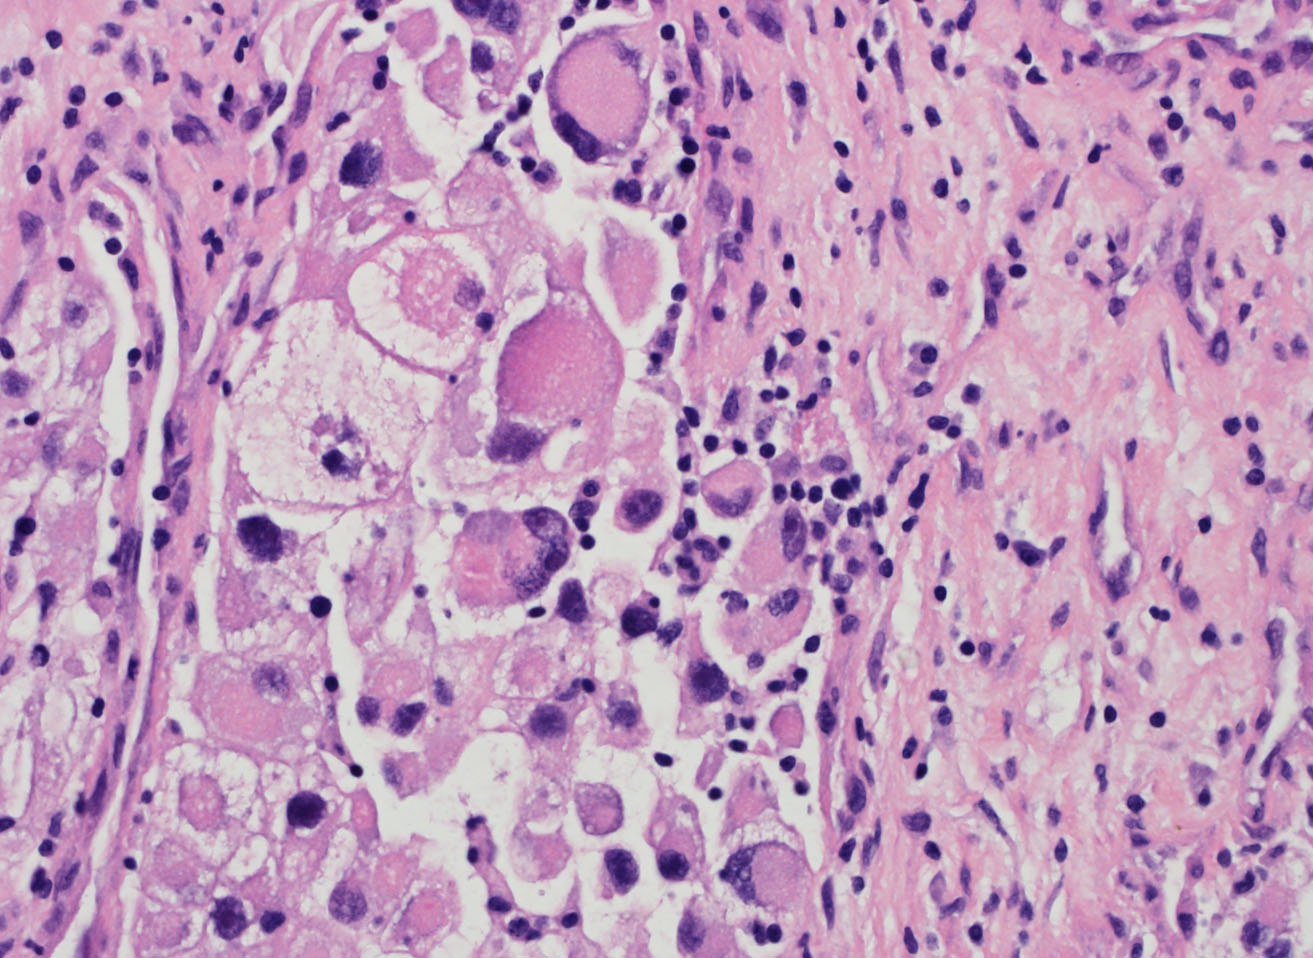

Classification of renal tumors

Case ID: 686